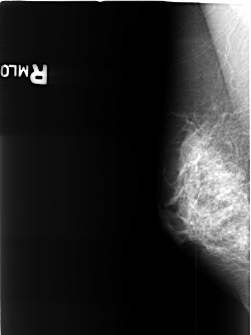

B_3426_1.RIGHT_MLO

RIGHT_CC LINES 4488 PIXELS_PER_LINE 3048 BITS_PER_PIXEL 12 RESOLUTION 50 NON_OVERLAY

RIGHT_MLO LINES 4016 PIXELS_PER_LINE 3008 BITS_PER_PIXEL 12 RESOLUTION 50 NON_OVERLAY